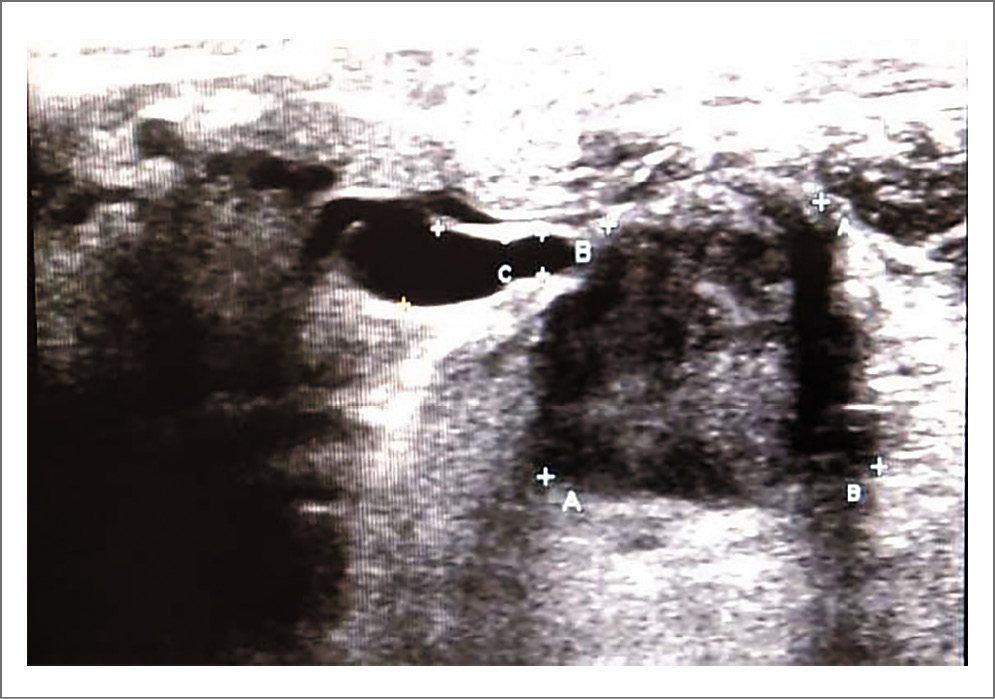

Выполнено ультразвуковое исследование периферических лимфоузлов 08.10.2021; картина представлена на рис. 5–8.

Рис. 5. Лимфоузлы справа: определяются множественные мелкие лимфоузлы с неизмененной структурой. Максимальный продольный размер в поднижнечелюстной области 22 мм. В режиме центрального дуплексного картирования кровоток определяется в виде отдельных цветовых локусов в области ворот лимфоузла.